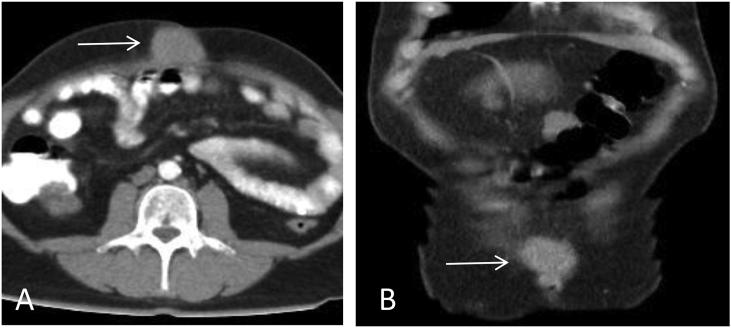

We describe the case of a 53-year-old patient with a diagnosis of prostate adenocarcinoma who underwent laparoscopic radical prostatectomy plus lymphadenectomy, staged as PT3BN0 (0/6) M0R1 Gleason 4 + 5. The patient never had negative PSA levels after the treatment, and presented elevation of the same, so radiotherapy was performed at a dose of 66 Gy plus antiandrogen deprivation therapy with leuprolide acetate for 30 months, with a decrease in PSA to 0.011 ng/ml, which remained stable. After 3 months of hormonal therapy, he presented with an umbilical mass on the scar of the laparoscopic port; ultrasound and computed tomography were performed, showing a solid mass dependent of the umbilical upper edge with a defect in the abdominal wall of 3 cm, as well as hepatic nodules suggestive of metastatic lesions and peritoneal implantations.

我们描述了一例53岁诊断为前列腺腺癌的患者,该患者接受了腹腔镜根治性前列腺切除术加淋巴结清扫术,分期为PT3BN0(0/6)M0R1,Gleason评分4 + 5。患者治疗后PSA水平从未呈阴性,且出现升高,因此进行了66 Gy的放疗,并联合使用醋酸亮丙瑞林进行30个月的抗雄激素剥夺治疗,PSA降至0.011 ng/ml并保持稳定。激素治疗3个月后,他在腹腔镜端口瘢痕处出现脐部肿块;进行了超声和计算机断层扫描,显示一个附着于脐上缘的实性肿块,腹壁有3 cm缺损,以及提示转移灶和腹膜种植的肝结节。